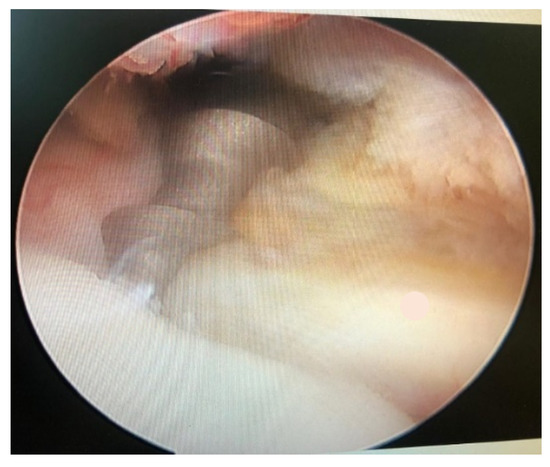

Posterior Shoulder Dislocation with Engaging Reverse Hill–Sachs Lesion: A Retrospective Study of Ten Patients Treated with Arthroscopy or Open Reduction and Stabilization

Ippolito, G.; Zitiello, M.; De Marinis, G.; D’Angelo, F.; Surace, M.F.; Ronga, M.; Sepe, V.; Garro, L.; Faoro, L.; Ferraro, S. Posterior Shoulder Dislocation with Engaging Reverse Hill–Sachs Lesion: A Retrospective Study of Ten Patients Treated with Arthroscopy or Open Reduction and Stabilization. J. Clin. Med. 2021, 10, 1410. https://doi.org/10.3390/jcm10071410